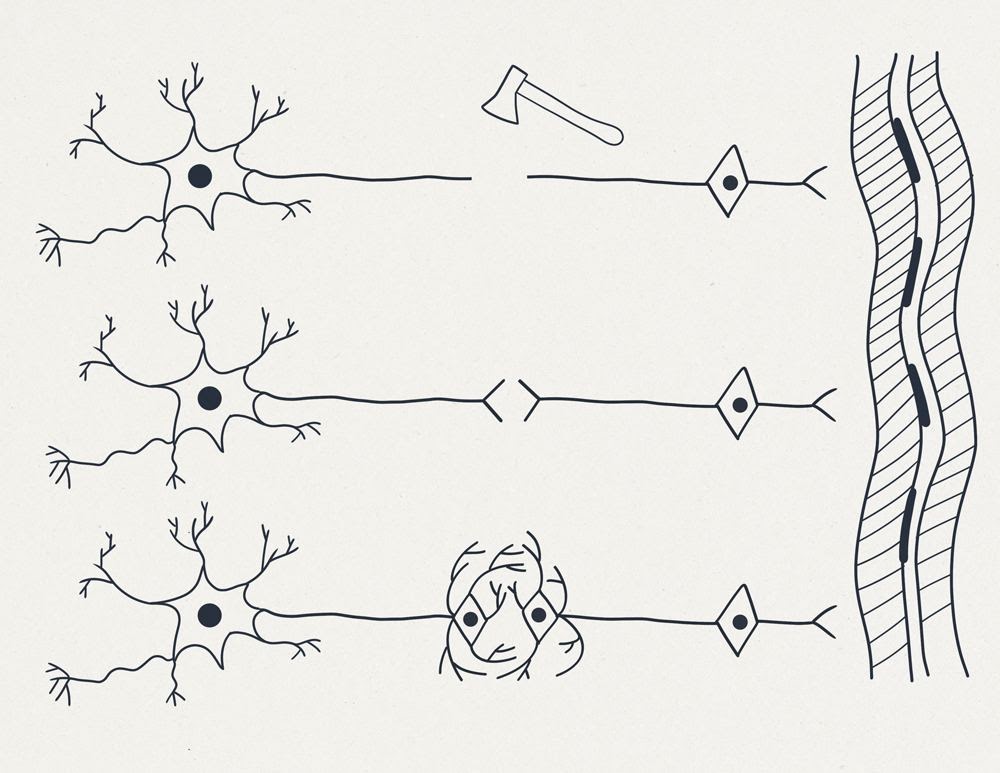

На рисунке 1 (см. выше) схематично представлены:

-

Справа – вертикально многоядерный фрагмент поперечнополосатой мышцы.

-

Вверху – две схемы “типичных нейронов”: можно обратить внимание на то что форма отростков второго нейрона – называется “Т-образной”.

-

Далее схематично изображен “топор”, перерубающий нерв или спинной мозг и отсекающий от одного из пострадавших нейронов фрагмент длинного отростка аксона. Фрагмент клетки, лишённый ядра, и многих других жизненно важных частей стойко теряет свои функции и способность к регенерации.

-

В нижней части рисунка изображен “нейрон будущего”, имеющий на периферии второе запасное ядро.